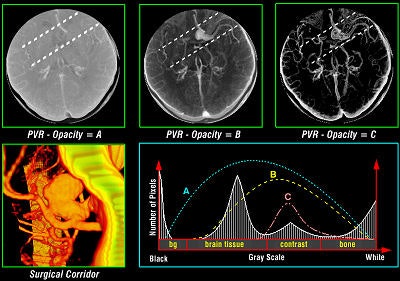

Tomographic examination of pathologies is currently performed by slice-based visual inspection despite the volumetric nature of the anatomical components, tumors/lesions, and imaging modalities. The reason for this could be the radiologist's 2D-based training for distinguishing between normal and abnormal tissue. The introduction of 3D imaging and augmented reality has prompted a huge interest in the utilization of such technology. Virtual endoscopic systems based on perspective rendering have been developed to allow the physician to "fly through" the patient's anatomy. Using such methods, the physician can reduce the opacity of certain tissues (such as the brain) to look at the internal structures (see figure 5, below).

Various volumetric imaging modalities have matured into systems that permit the physician to visualize and quantify the extent of disease in volumetric form to plan therapeutic interventions. 3D imaging techniques greatly enhance a surgeon's ability to create plans prior to surgery, follow preoperative plans during surgery, and modify plans based on intraoperative information (see figure 6, below).

![]() |

| Figure 6 |

Such techniques decrease the amount of invasiveness and exploration during surgery. Researchers have developed software for some operations to aid in presurgical planning and to simulate proposed treatments based on biological models. For example, orthopedic planning systems use a 3D model of the prosthesis in conjunction with the patient's data to determine the optimal placement (location and shape of cavity) for the prosthesis in the bone. Stent graft measurements are made prior to operation to design the graft based on the contours of a vessel.

Path-planning techniques have been applied to neurosurgery to determine the optimal path for a surgical instrument or radiation beam. These methods generally input a geometric description of the relevant structures and a cost function associated with damaging any of these structures. They then produce a surgical plan that minimizes the cost function.